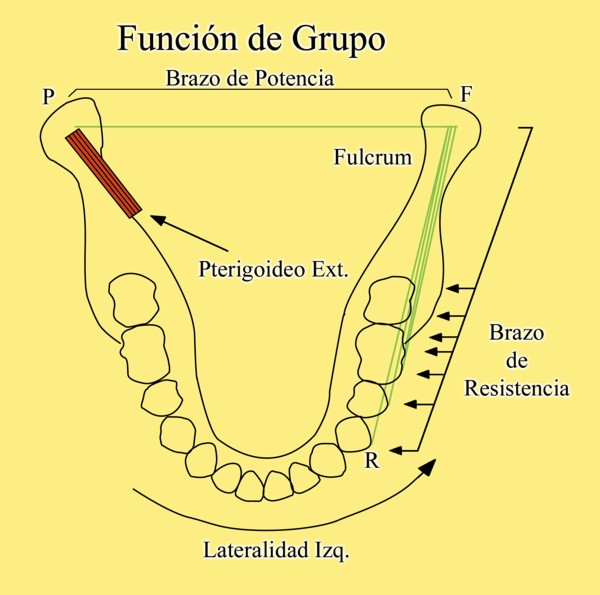

En un esquema de lateralidades a la izquierda, observamos que el Fulcrum de la misma lo encontramos en el cóndilo izquierdo, Cóndilo de Trabajo, la Potencia se encuentra en la fuerza generada por el Pterigoidéo Ext. del lado derecho, Cóndilo de No Trabajo, y la resistencia se dispone, en el caso de una FUNCIÓN DE GRUPO, en las Crestas Triangulares Internas de la tabla premolar-molar superior, que rozan contra las Crestas Centrales antagonistas ,correspondientes al inferior.

Por lo tanto, el Brazo de Potencia se establece entre el CnT(POTENCIA),y el CT(Fulcrum), mientras que los Brazos de Resistencia de las distintas piezas que intervienen en la Función de Grupo, se encuentran entre estas piezas y el CT(Fulcrum).

Como podemos ver en el esquema, estos son menores que el Brazo de Potencia y por lo tanto la fuerza generada por el mismo, producirá mayor deterioro , pues la palanca no está equilibrada:

EL BRAZO DE POTENCIA ES MAYOR QUE EL DE RESISTENCIA (Fig.6)